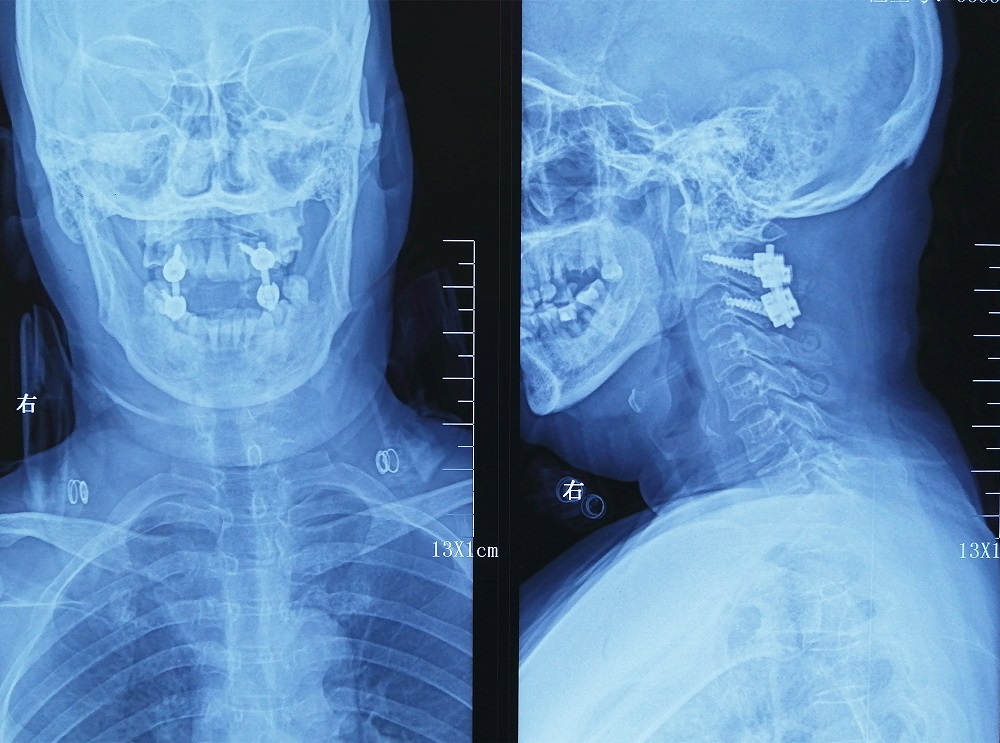

术前准备各项完成后,廖博主任亲自为马女士手术,不仅全切肿瘤,而且为了保持颈椎的稳定性,不影响以后的正常生活,同时实施了植骨融合内固定术。手术很成功,术后马女士症状明显消失,康复后的马女士已于近日出院。

术后影像学检查